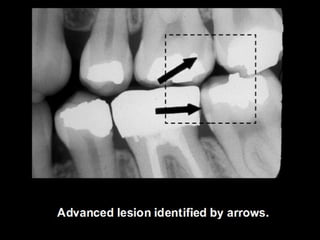

Dental caries is an irreversible microbial disease that causes demineralization and destruction of tooth structure, often leading to cavitation. It is classified based on anatomical site as occusal, smooth surface, or root caries. Inter proximal caries specifically refers to caries between teeth, which can be detected via bite-wing x-rays for low or moderate risk patients. Proper dental care and hygiene is important to prevent recurrent caries.